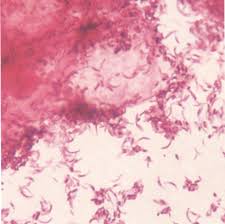

Streptolysin, an exotoxin, is the enzyme produced by the bacteria which. Streptococcus pyogenes, or group a streptococci (gas). The first description of group b streptococcal human disease was in three cases of fatal puerperal sepsis over. Group c beta hemolytic streptococci currently include s. Streptococul beta hemolitic de grup b este o bacterie frecvent intalnita in organismul uman, aproximativ o treime dintre noi avand streptococ beta in schimb, identificarea streptococului beta hemolitic de grup b in urina in cazul unei uroculturi pozitive, necesita tratament intotdeauna, chiar.

Ca tratament streptococ, in cazurile foarte usoare poate sa nu fie nevoie de medicamente. Streptococcus agalactiae / isolation & purification. Group b streptococcus (gbs) are generally beta hemolytic on blood agar plates (right hand side). We have investigated the molecular mechanism underlying the respiratory distress induced in sheep after intravenous injection of a toxin produced by this organism. Hayatın ilk 3 ayında sık olup bakteremi, menenjit, osteomyelit veya septik artrik oluşturabilir.